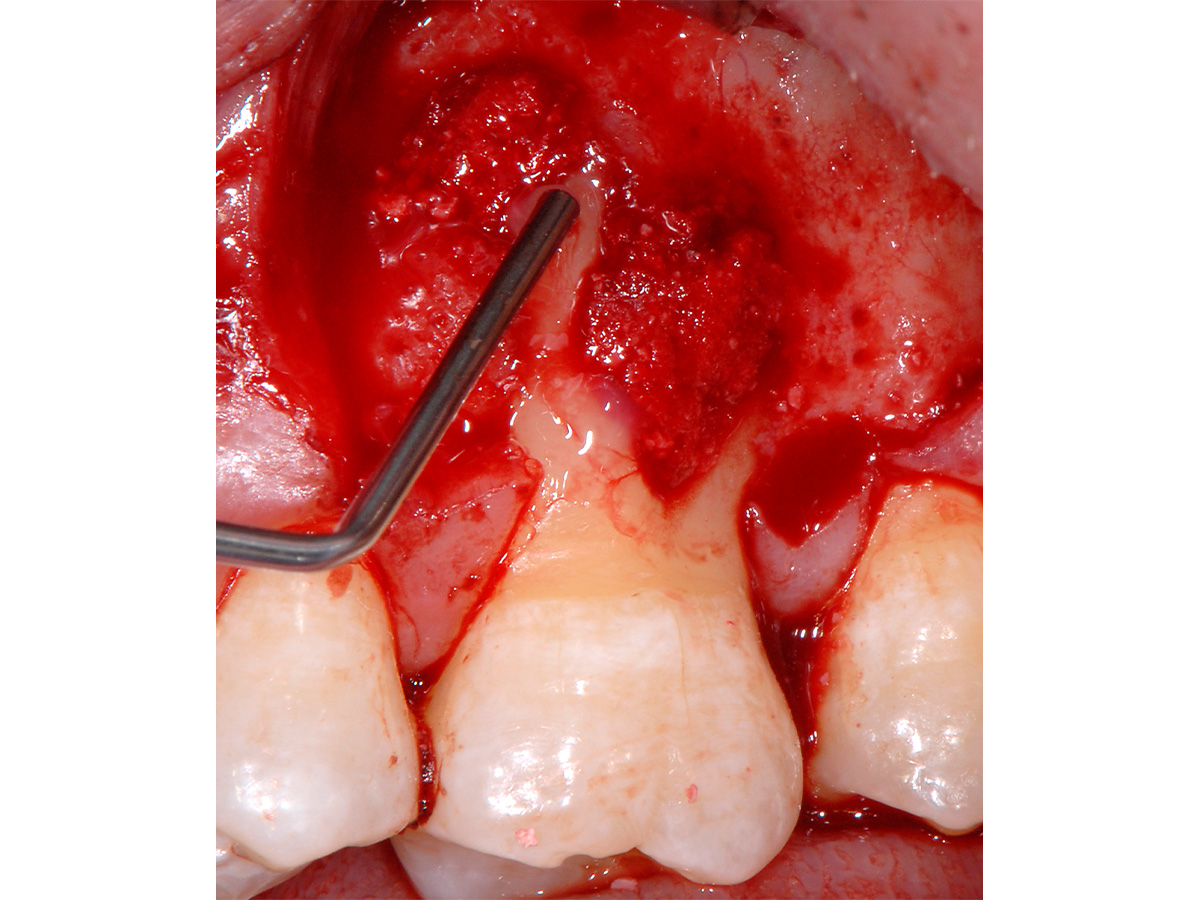

Abbildung 4

Hartgewebsbearbeitung: Bearbeitung der Wurzeloberflächen mit Hand- und Ultraschallinstrumenten im Bereich des parodontalen Defektes.